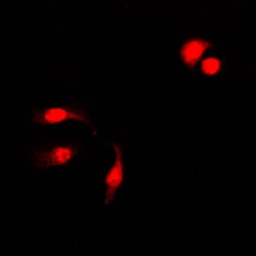

ICC/IF analysis of formalin-fixed HeLa cells using GTX32222 NFkB p105 (phospho Ser927) antibody.

Red : Primary antibody

Blue : DAPI

Permeabilization : 0.1% Triton X-100 in TBS for 5-10 minutes